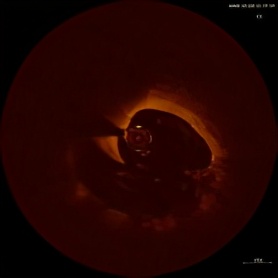

黄某,男,39岁,“因反复胸闷,心悸10天”入院,上周冠脉造影提示左回旋支近段99%局限性狭窄,右冠近段30%狭窄(可疑不稳定斑块),上周对回旋支病变植入一枚支架,但右冠病变是否需要处理仅凭造影不能明确。今日行OCT检查,提示右冠近段病变实际上为冠脉夹层伴有菲薄的脂质纤维帽,在OCT指导下,顺利为患者病变处植入一枚支架,术后OCT结果显示支架贴壁良好,夹层消失,术后患者胸闷明显改善。

薄纤维帽

冠脉夹层

术前

OCT在识别、支架贴壁、支架的内膜撕裂,以及内膜对支架的覆盖、斑块性质的判断以及薄纤维帽的识别方面是目前最优的方式。但OCT的问题是穿透深度较短,只有1到2毫米。而IVUS分辨率较低,但其穿透深度可达到4到5毫米。

新一代OCT成像系统FD-OCT最大的优点是更高速度的扫描,每秒种的扫描帧数为100帧,回撤速度大于20mm/S,每次操作只需注射一次造影剂就可完成冠脉血管的成像,提高了操作安全性。OCT可清晰显示内膜下的病变和斑块,识别易损斑块、稳定斑块、血栓、钙化、夹层、支架及支架表面的内膜增生和支架内再狭窄,因此在评价斑块的性质、介入治疗的指导、再狭窄机制临床研究和疗效评价方面,有着独到的优势和应用价值。